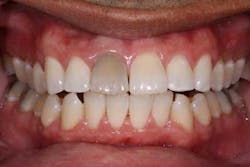

Of all the problems that can occur with implant placement in the anterior, not controlling the zenith of gingival contour may be the most troublesome when it comes to anterior esthetics. Gingival zenith or height of gingival contour is defined as the apex of the gingival height. There are many ways to lose several millimeters of peri-implant mucosa, and it has been shown that even a 1 mm apical displacement of peri-implant mucosa may result in insurmountable limitations in anterior implant esthetics. Things such as deep implant placement, buccal resorption, and relative tooth eruption are just some of the things that can cause this loss of tissue.

When planning surgery with my periodontist, we both decide where we want the zenith to be esthetically, and then plan implant placement 3 mm apical and 2 mm palatal to this location. Biologically speaking, this location will allow us to preserve the zenith from a placement standpoint. Keep in mind that we need to have the tissue healthy and under control prior to starting any procedure.

Now comes the tricky part — the provisional. Prosthetic control of peri-implant tissue is achieved by properly utilizing your abutment and provisional form. When placing the provisional, it is important to maintain gingival zenith. When fabricating a provisional, my rule of thumb is to create a flat or slightly convex surface facially and lingually, and a concave surface interproximally. This will minimize impingement on the tissue interproximally and, if anything, allow for “overgrown tissue” to develop. This tissue can be easily contoured prior to final placement to give an ideal esthetic gingival architecture.